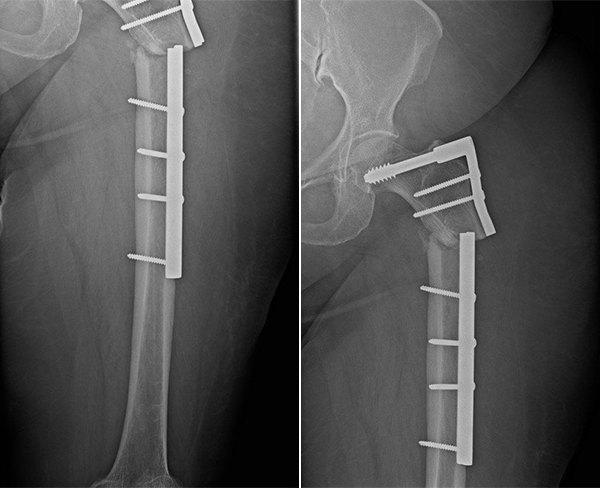

La prezentarea în cadrul Spitalului Multidisciplinar Arcadia, pacienta acuza dureri importante la nivelul coapsei stângi, atât în repaus, cât și la mobilizare, asociate cu imposibilitatea sprijinului pe membrul inferior afectat. Examinarea imagistică a evidențiat ruperea plăcii metalice și lipsa vindecării fracturii, cu apariția unei pseudartroze, o complicație în care capetele osoase nu se mai unesc, iar în zona fracturii se formează o articulație falsă ce împiedică consolidarea normală a osului.

Imaginea 1. Examinare imagistică a pseudartrozei de femur proximal